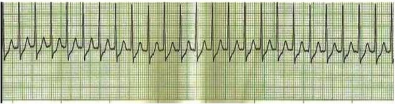

Homem de 44 anos é admitido na emergência com malestar e palpitação. Ao exame físico, apresentava FC 180 bpm, PA 122x81 mmHg, SatO2 97% em ar ambiente. Realizou eletrocardiograma de 12 derivações que revelou o ritmo abaixo. Qual conduta inicial deve ser adotada nesse caso?